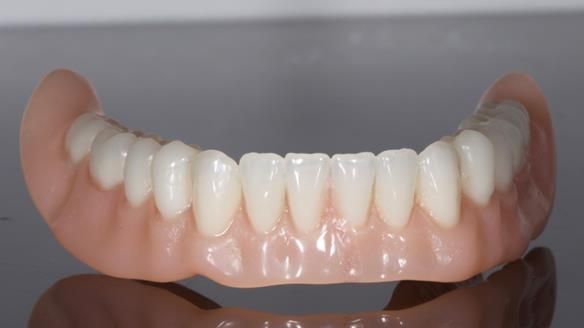

In this edition, I present the complete denture treatment for Kate, a 69-year-old American woman living in Garstang, UK. Kate had been edentulous for many years and required a set of complete dentures that closely mimicked her natural teeth. The new upper and lower dentures provided excellent retention and stability, with significant suction in the upper denture. Below, I detail the step-by-step process of her treatment, as well as my workflow for implant-supported overdentures for patients who may require them.

• The lower denture being unstable and rocking

• Stability in the lower denture

The treatment was a resounding success, meeting all of Kate’s expectations. While I was confident I could achieve a natural appearance, the challenges of gagging, denture stability, and eating were less predictable and uncertain. I discussed these concerns thoroughly at the outset, and Kate decided to proceed despite the high cost. She expressed that there was no pressure to move forward with the treatment, and she’s been delighted with the life-changing results.

Treatment Process: I provided the clinical work while Rowan Garstang and Sam Hesketh delivered the technical aspects. The treatment required fifteen visits to fit and review Edgar.